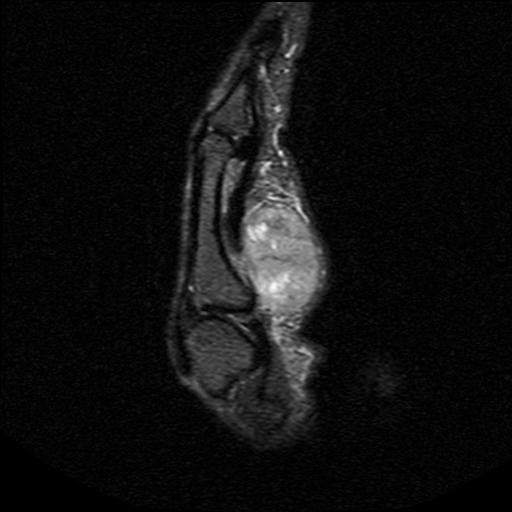

Talus

1. Head and neck

- medial approach between Tibialis anterior and Tibialis posterior

2. Body

- lateral Ollier's approach between Peroneus tertius and Peroneus brevis